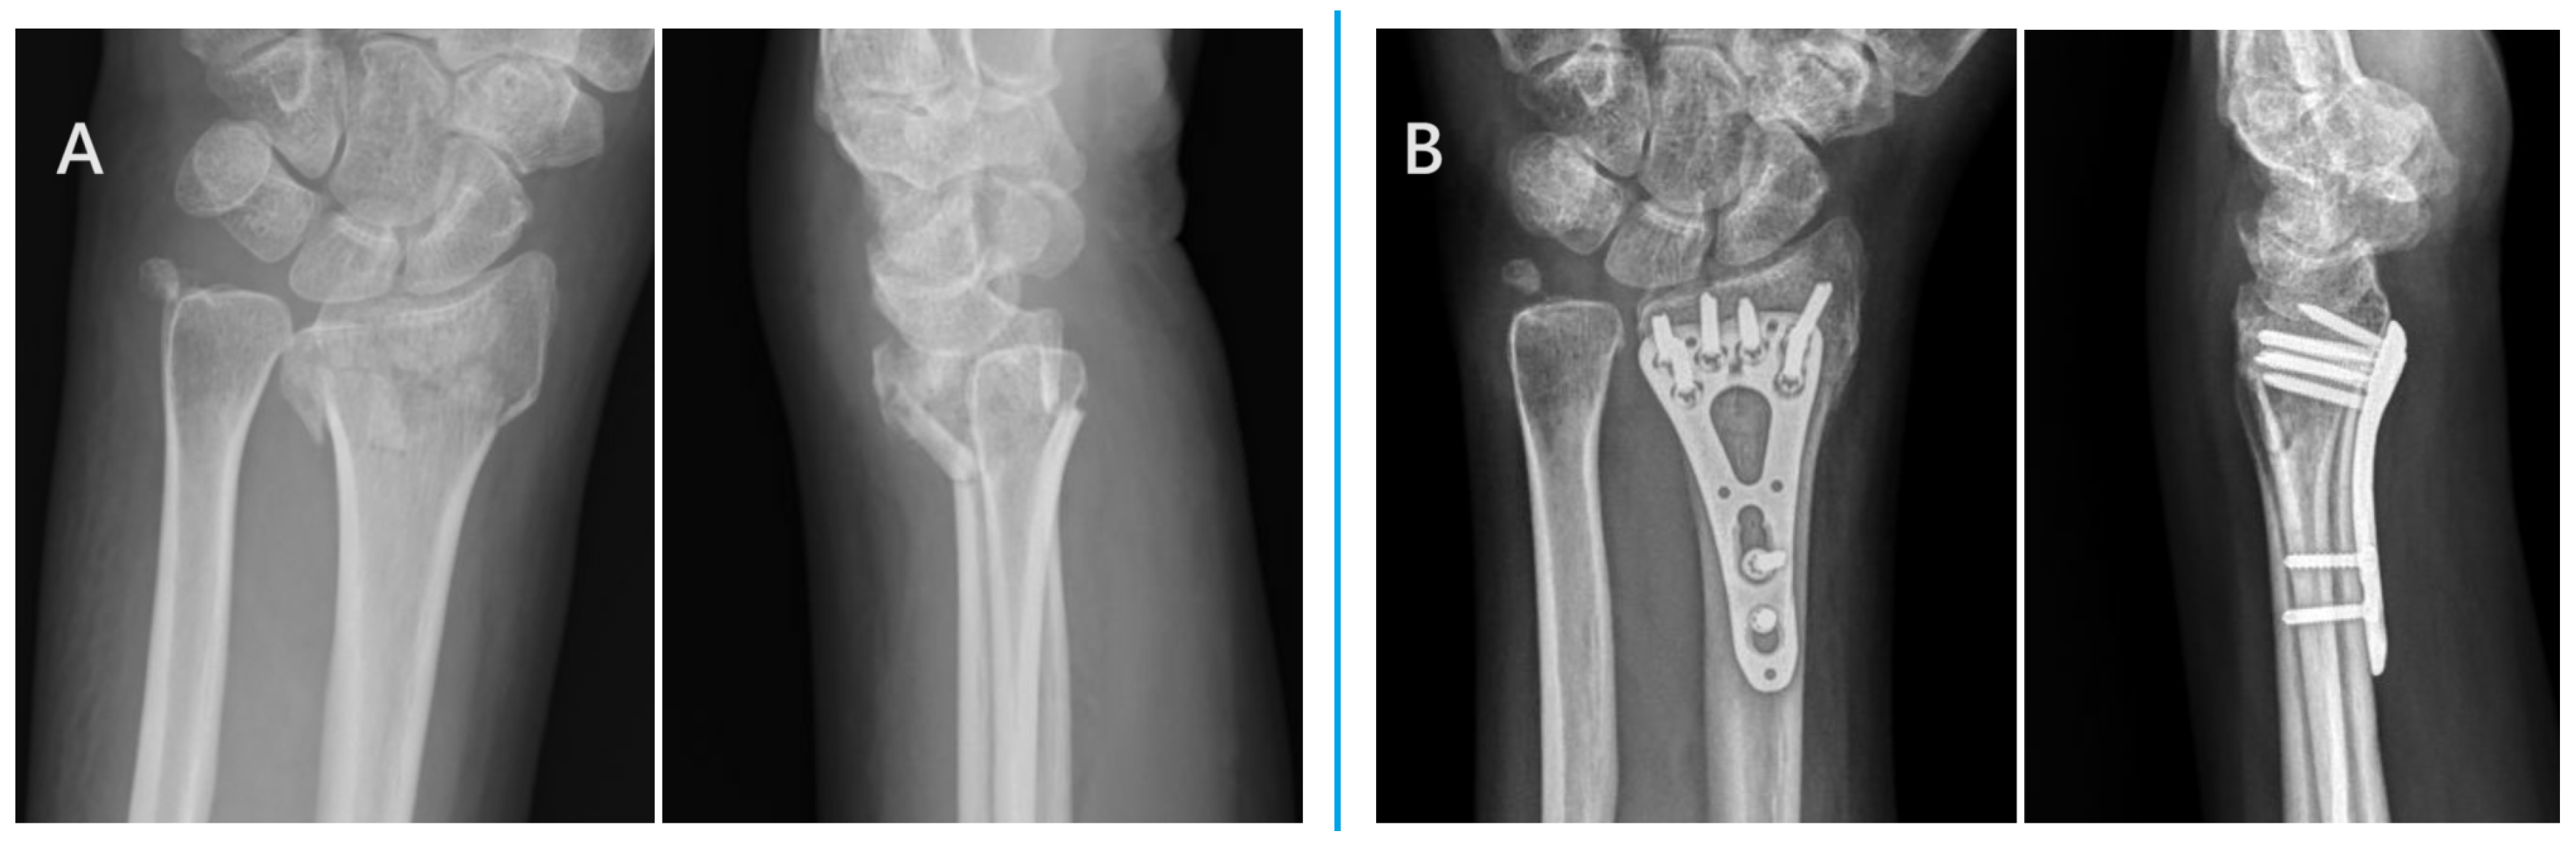

2.2. Surgical Techniques of Ultimate Incision Surgery

2.3. Surgical Techniques of Conventional Incision Surgery